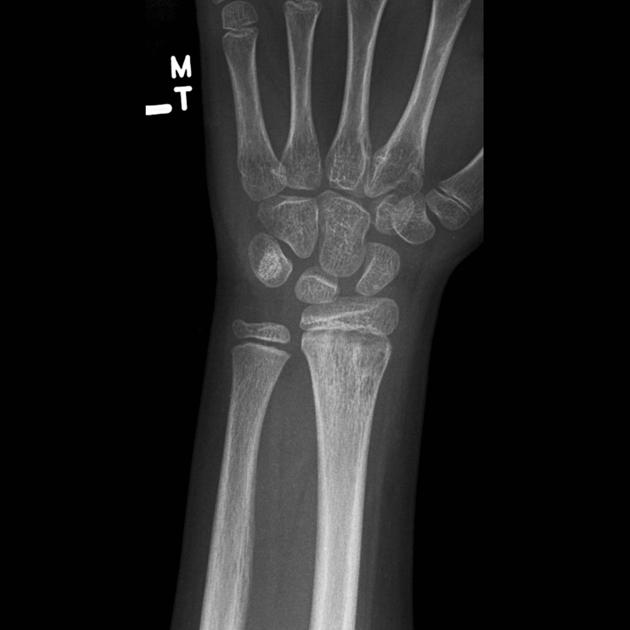

Инструментальная диагностика начинается с обзорной рентгенографии лучевой кости в двух проекциях, которая может выявить остеопороз, очаги остеолиза, периостальную реакцию и секвестры, однако на ранней стадии изменения могут отсутствовать. При недостаточной информативности проводится компьютерная томография костей, позволяющая точно оценить структуру кости, наличие секвестров и зону деструкции. Наиболее чувствительным методом в ранней диагностике является магнитно-резонансная томография суставов, дающая возможность визуализировать отёк костного мозга, вовлечение мягких тканей и субпериостальные скопления.

Рентгенологическая диагностика остеомиелита лучевой кости направлена на выявление прямых признаков инфекционно-деструктивного поражения костных структур запястья и пястных костей. Исследование проводится в прямой и боковой проекциях в режиме обзорной рентгенографии с прицельной съёмкой лучезапястного сустава и кисти, охватывающей весь объём поражённых костей.

Рентген выявляет следующие анатомические признаки:

- В прямой проекции при обзорной рентгенографии определяется зона остеолиза с нечёткими границами в области пястных костей или костей запястья, сопровождающаяся нарушением непрерывности кортикального слоя и снижением общей рентгеновской плотности поражённого участка.

- На боковой рентгенограмме визуализируется периостальная реакция в виде наслоения на поверхности кости, истончение или вздутие кортикальной пластинки, а также возможное смещение анатомических контуров за счёт деструктивного процесса.

- При прицельной съёмке определяются секвестры — плотные включения с чёткими контурами, отделённые от основной костной ткани, наличие склеротического ободка по периферии и возможные признаки хронического течения с формированием свищевых каналов.

Рентгенографическое исследование позволяет детально визуализировать следующие диагностические параметры остеомиелита лучевой кости:

Локализация и протяжённость костного дефекта с точным определением вовлечённого сегмента (пястные, запястные кости, фаланги).

Характер и тип периостальной реакции, отражающей фазу воспалительного процесса и позволяющей судить о его активности.

Наличие, форма и количество секвестров, их размеры и степень отграниченности от интактной кости, что критично для стадирования остеомиелита.

Уровень деструкции кортикального слоя и глубина поражения губчатого вещества, позволяющие оценить тяжесть и прогрессирование заболевания.

Степень вовлечения суставных поверхностей, в том числе межзапястных и запястно-пястных сочленений, с возможной эрозией и деформацией.

Рентгенологическое обследование имеет ряд ограничений, и с его помощью не всегда удаётся точно визуализировать следующие аспекты остеомиелита лучевой кости:

- Ранние воспалительные изменения, возникающие до появления костной деструкции, не фиксируются на рентгенограммах в первые дни заболевания.

- Состояние костного мозга, включая отёк, инфильтрацию или абсцедирование, не отображается при стандартной рентгенографии.

- Поражение параоссальных мягких тканей, гнойные затёки и свищевые ходы остаются недоступными для визуализации в пределах обычного снимка.

- Трудности интерпретации в зонах с наложением анатомических структур, особенно в области запястья, могут затруднить точную локализацию процесса.

- Присутствует лучевая нагрузка: при выполнении рентгенографии руки в прямой и боковой проекциях с применением прицельной съёмки зоны поражения суммарная эффективная доза составляет от 0,01 до 0,03 мЗв.